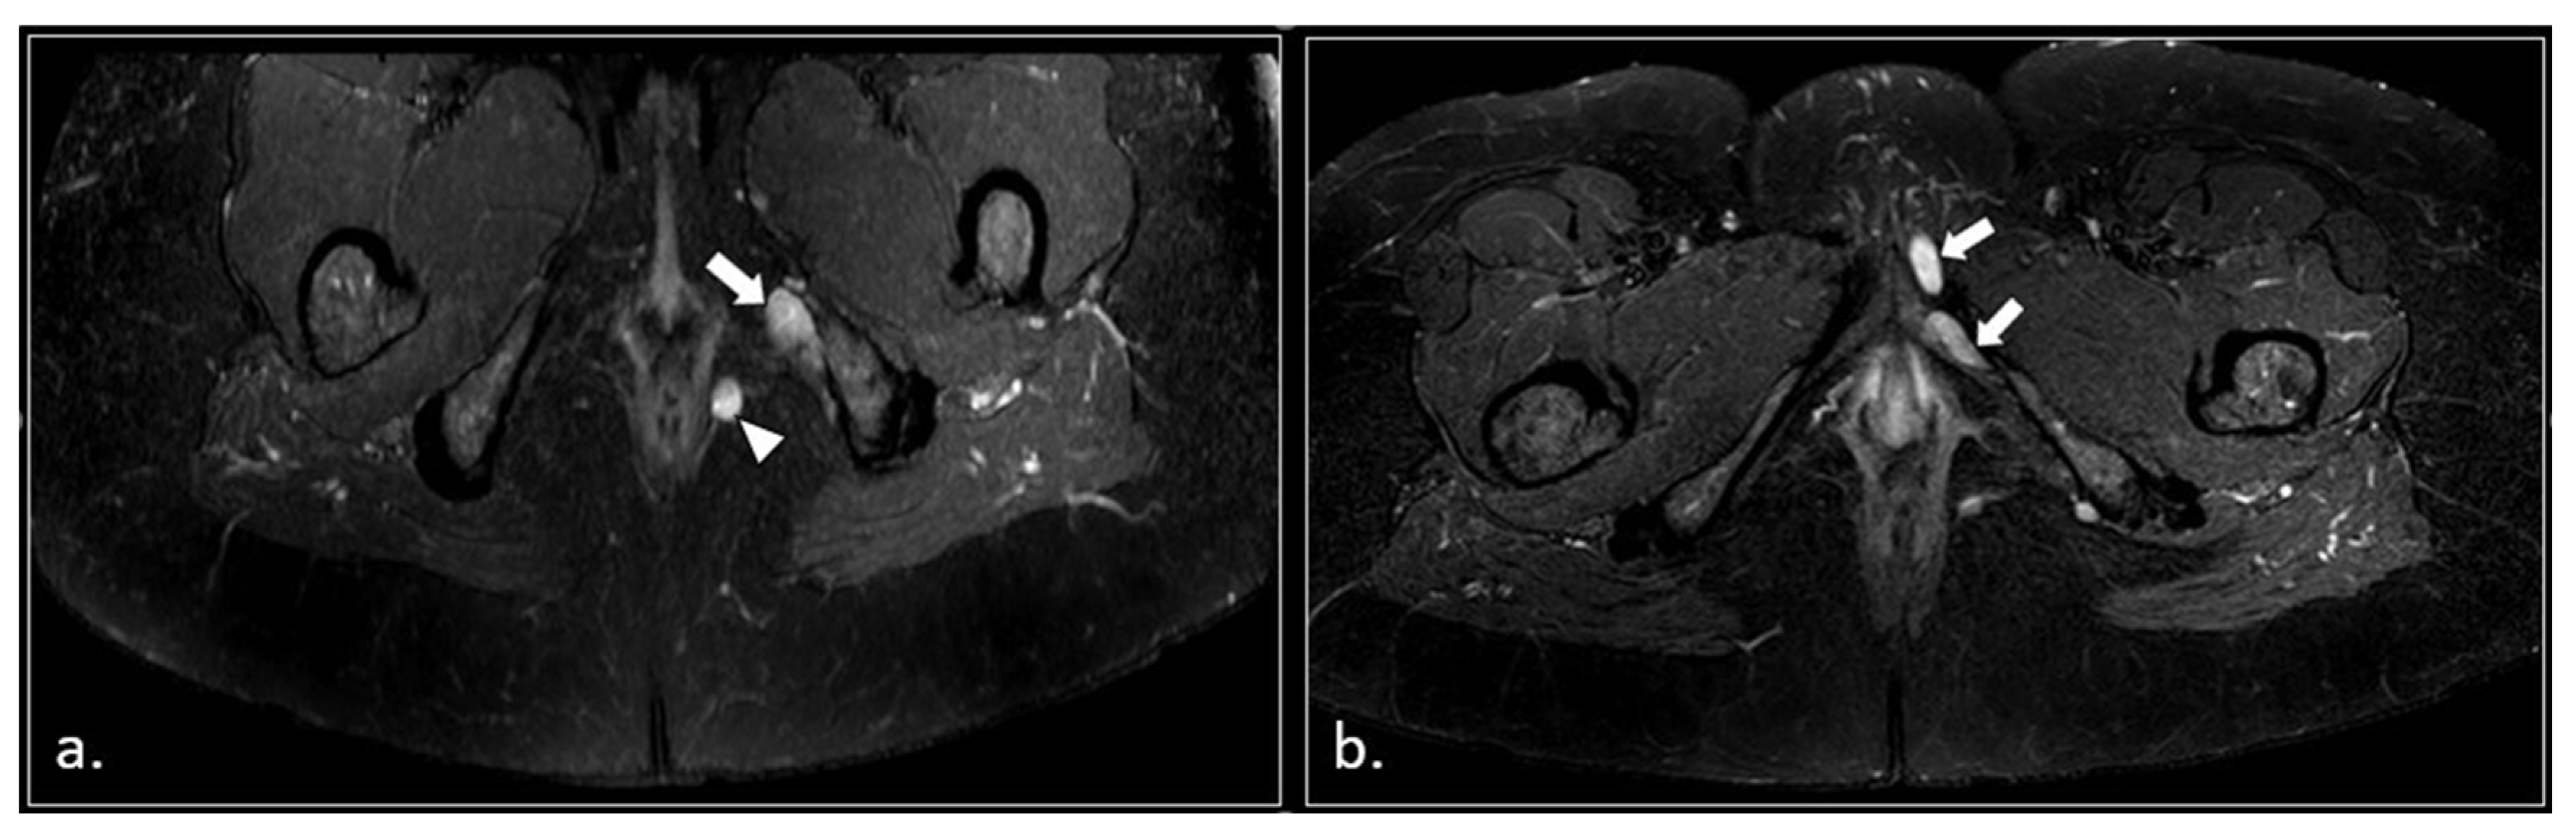

Figure 7.

(a) Axial T2-weigthed section through the distal Alcock’s canal shows an atrophy of the left pubo-coccigeal muscle (arrow) and paravaginal fibrosis on the same side. (b) A more cranial section shows with better advantage the paravaginal fibrosis (arrow); the wall of the vagina is stretched (arrowhead). (c) b600 DWI section, acquired at the same level of (b), shows a strong hyperintensity and enlargement of the left pudendal nerve (arrow).

Figure 8.

50-years-old female with chronic pudendalgia. (a) STIR Maximum Intensity Projection (MIP) image demonstrates schwannomas of the left pudendal nerve (arrow) and inferior rectal nerve (arrowhead). (b) A lower section shows two schwannomas of the distal branches of the left pudendal nerve (arrow).